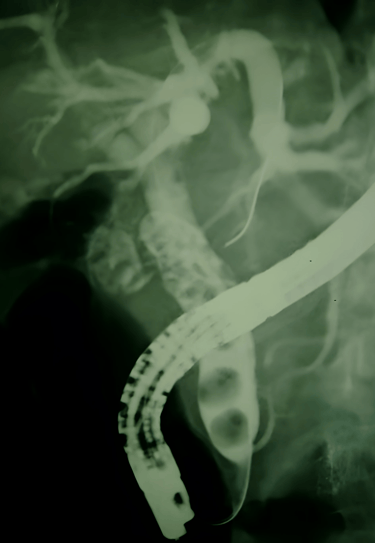

Colangiopancreatografía endoscopica (CPRE)

Colangiopancreatografía endoscópica o CPRE

Extracción de litos (litos en la vía biliar o coledocolitiasis)

Colocación de protesis temporales o definitivas

Biopsia y cepillado de tumor pancreatobiliar

Endoscopia de Vías Biliares

Coledocolitiasis múltiple